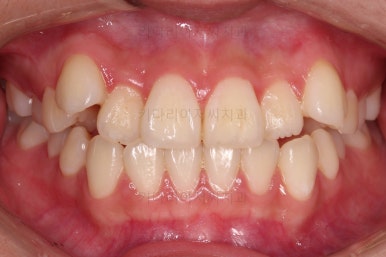

연산동교정치과 교정장치 부착 직후의 모습입니다.

장치가 보이는 느낌이나 입매가 바뀌는 느낌 참고 바랍니다.

이번 환자분은 교정장치를 부착했다해도 거의 입매가 바뀌지 않는 분입니다.